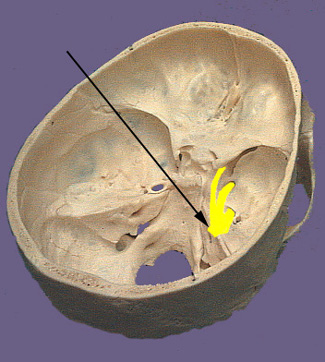

Cranium CN V

The trigeminal nerve as the name indicates is composed of three large branches.  They are the ophthalmic (V1, sensory), maxillary (V2, sensory) and mandibular (V3, motor and sensory) branches.  The large sensory root and smaller motor root leave the brainstem at the midlateral surface of pons. The sensory root terminates in the largest of the cranial nerve nuclei which extends from the pons all the way down into the second cervical level of the spinal cord. The sensory root joins the trigeminal or semilunar ganglion between the layers of the dura mater in a depression on the floor of the middle crania fossa.  This depression is the location of the so called Meckle's cave.   The motor root originates from cells located in the masticator motor nucleus of trigeminal nerve located in the midpons of the brainstem. The motor root passes through the trigeminal ganglion and combines with the corresponding sensory root to become the mandibular nerve. It is distributed to the muscles of mastication, the mylohyoid muscle and the anterior belly of the digastric. The mandibular nerve also innervates the tensor veli palatini and tensor tympani muscles. The three sensory branches of the trigeminal nerve emanate from the ganglia to form the three branches of the trigeminal nerve.  The ophthalmic and maxillary branches travel in the wall of the cavernous sinus just prior to leaving the cranium.  The ophthalmic branch travels through the superior orbital fissure and passes through the orbit to reach the skin of the forehead and top of the head. The maxillary nerve enters the cranium through the foramen rotundum via the pterygopalatine fossa. Its sensory branches reach the pterygopalatine fossa via the inferior orbital fissure (face, cheek and upper teeth) and pterygopalatine canal (soft and hard palate, nasal cavity and pharynx). There are also meningeal sensory branches that enter the trigeminal ganglion within the cranium.  The sensory part of the mandibular nerve is composed of branches that carry general sensory information from the mucous membranes of the mouth and cheek, anterior two-thirds of the tongue, lower teeth, skin of the lower jaw, side of the head and scalp and meninges of the anterior and middle cranial fossae.